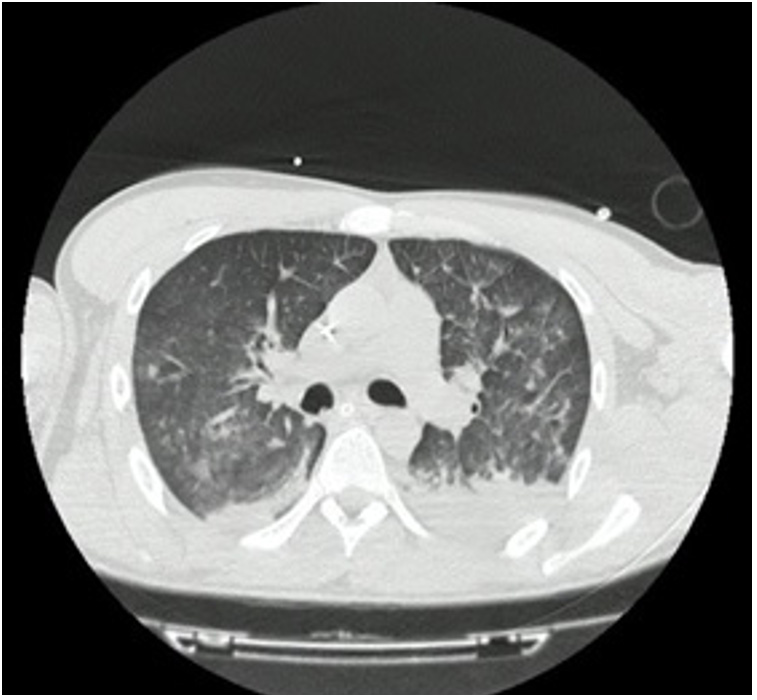

Por lo anterior, se trasladó el paciente a tomografía, donde se le realizó una imagen de tórax de alta resolución (figura 1), asociada con angiotomografía de cráneo, que evidenció un derrame pleural bilateral con patrón de empedrado. La imagen del cráneo no mostró cambios.

Figura 1 Tomografía de tóraxSe aprecia un engrosamiento liso de los tabiques interlobulillares asociados con opacidades en “vidrio esmerilado” centrales y consolidaciones difusas, principalmente en las zonas dependientes. Engrosamiento de las paredes bronquiales. Derrame pleural bilateral